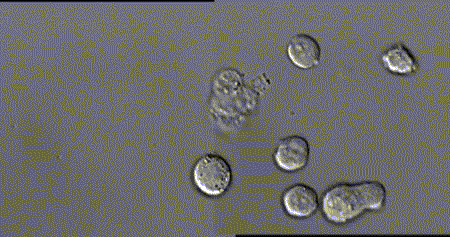

3.這張動圖顯示的是嗜酸性粒細胞在趨化作用的“感知”下逐漸聚集到一只秀麗隱桿線蟲周圍并對它進行攻擊的過程。有“成千上萬”的嗜酸粒細胞圍聚在線蟲周圍,就像一群螞蟻,善打“包圍戰(zhàn)”。

4.這是中性粒細胞追擊金黃色葡萄球菌的一個過程。免疫細胞捕捉細菌時超萌!